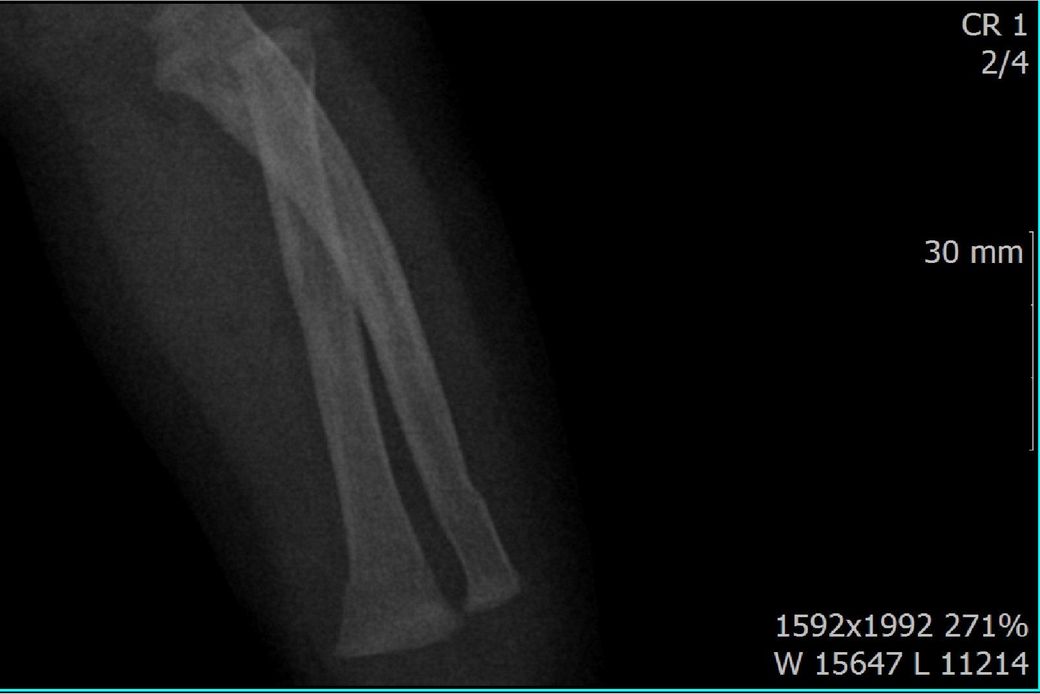

다름이 아니라, 첨부드린 엑스레이(X-ray) 사진처럼 골절 사실을 알게 되고 골절 발생 시점 대략적으로나마 추정시기를 파악하려고 문의 드리게 되었습니다

1) 3월 30일 촬영한 X-ray만으로 정확한 골절 시기를 100% 특정하는 데에는 한계가 있다는 점 충분히 인지하고 있기에 촬영날짜 기준으로 대략적으로 어느정도 시점에서 발생되었을 것으로 추측(ex 당일, 7~10일전, 7~14일 전, 10일 ~ 20일전, 14일 ~ 30일전 등등등)되는지 이해하고 싶습니다.

첨부드린 파일에는 없지만 4월 5일 사진에서는 캘로스 라는 것이 발견된다고 합니다.

• 1번 째 사진